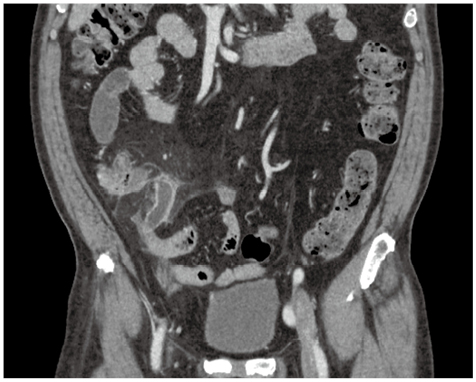

症例2

症例2の患者情報

60歳代,男性。

昼頃から右下腹部痛が出現し来院。前日夜から38℃台の発熱あり。WBC 10.9×103/μL,CRP 22.4mg/dL。

既往歴:糖尿病,胆石症。

身体所見:McBurney点を最強とする圧痛/反跳痛あり。